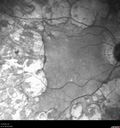

Heavy Panretinal photocoagulation for PDR - 1980s

64 year old female - images from 2018 - heavy PRP about 30 years ago

VA 20/20 OD, 20/50 OS